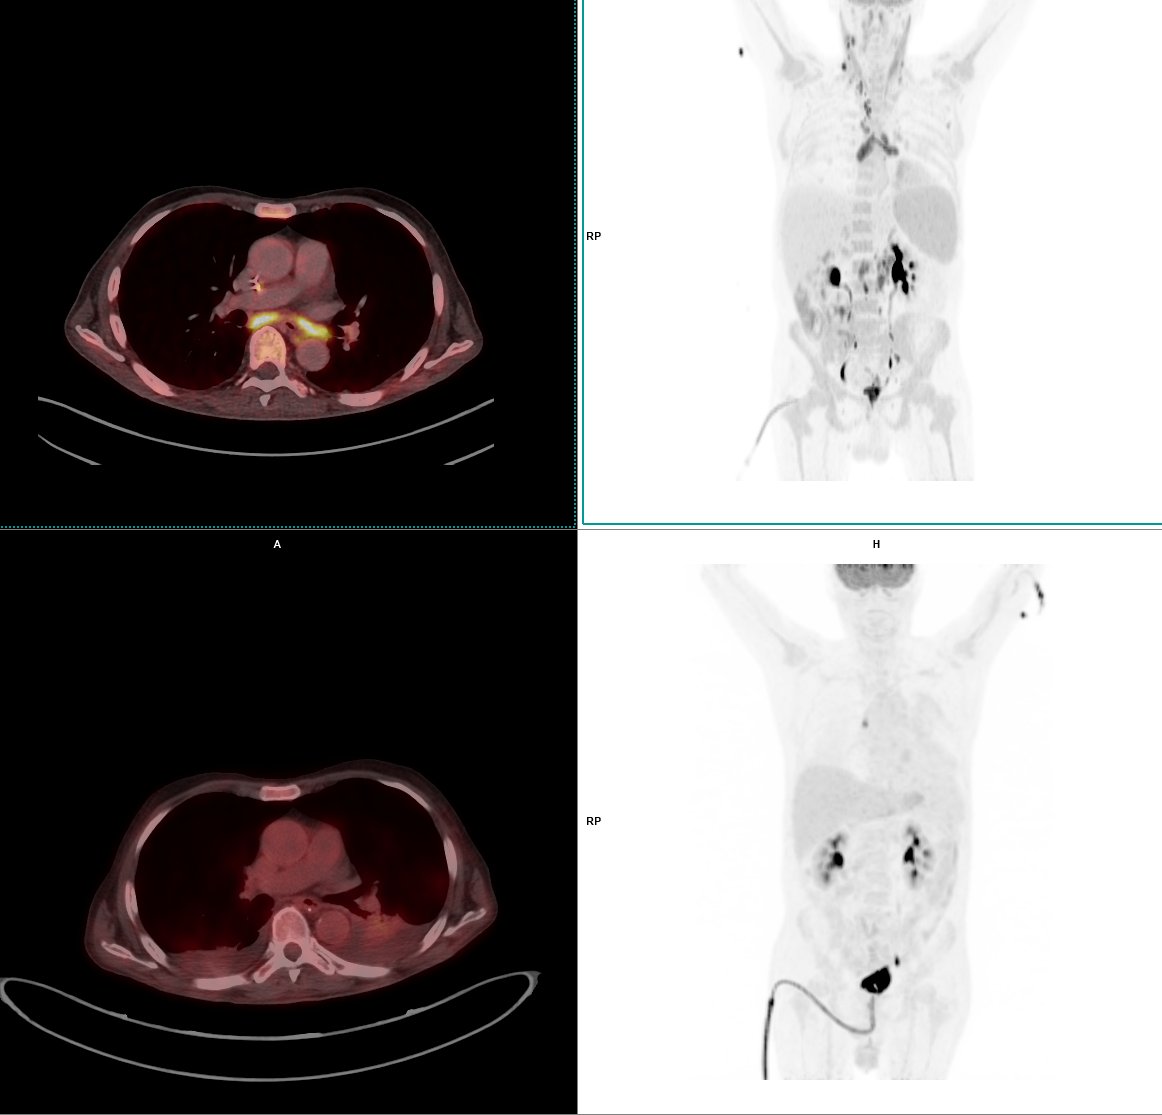

Frente a la sospecha o durante el tratamiento de un cáncer el PET-TC digital supone un avance diferencial, puesto que mejora en un 26,5% la detectabilidad de tumores subcentimétricos o microlesiones inferiores a 10 mm. De esta manera, con el nuevo equipo casos que inicialmente podían no detectarse y considerarse como falsos negativos pueden positivizarse y diagnosticarse correctamente. Así se acelera el tratamiento y se aumentan considerablemente las posibilidades de curación.

Los estudios de PET-TC son una combinación simultánea en un mismo procedimiento de dos técnicas. La tomografía axial computarizada o TAC que genera una representación por secciones de las estructuras internas del cuerpo y que unidas proporcionan una imagen tridimensional del organismo. Por su parte, el PET, siglas de tomografía por emisión de positrones, aporta un estudio sobre el funcionamiento de los órganos y detecta posibles cambios celulares. La combinación de la información metabólica con la anatómica permite a los especialistas confirmar un diagnóstico precoz de múltiples patologías, así como determinar el estadiaje o gravedad por ejemplo de tumores o procesos neurodegenerativos.

Las células tumorales consumen mayor cantidad de glucosa, puesto que necesitan más energía que las células sanas, para crecer más rápido. Bajo este precepto, al paciente se le inyecta glucosa en un radiofármaco que actúa como contraste y que resulta observable gracias a la tecnología del PET-TC. Así, se considera que en las zonas en las que se detecta mayor consumo de glucosa, puede existir patología tumoral, infecciosa o neurodegenerativa.

El nuevo equipo de medicina nuclear de Clínica Rotger permite realizar los estudios con mayor precisión y por lo tanto diagnosticar lesiones de tamaño inferior a 2mm, de forma precoz y en un estadiaje menos avanzado. El PET-TC digital también mejora la experiencia del paciente puesto que al disponer de un sistema de adquisición continuo de imágenes y estar dotado de Inteligencia artificial es más rápido, reduce el tiempo de los estudios prácticamente a la mitad y es mucho más preciso y sensible en la toma de imágenes.